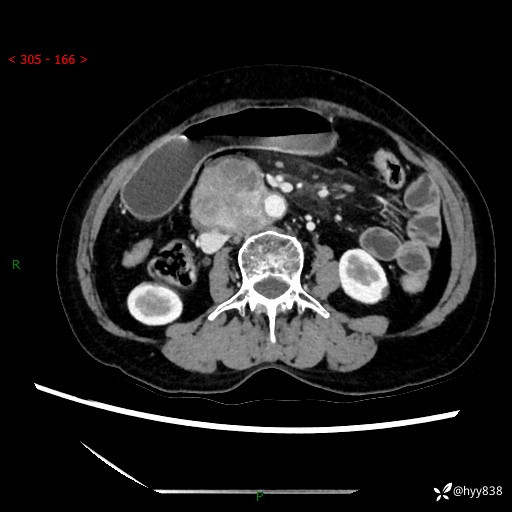

71岁/女,腹痛1月余。腹膜后肿物,间质瘤 VS 副节瘤 VS 平滑肌肉瘤---(有结果)

【患者信息】:71岁/女

【主诉】:腹痛1月余

【现病史及既往史】:患者于1月前无明显诱因出现右下腹部疼痛不适,呈阵发性隐痛,尚可耐受,放射至后背部及腰部疼痛,伴排便困难,不伴其它部位疼痛,无嗳气,无不洁饮食,无黑便,无恶心、呕吐、腹胀腹泻、呕血、发热、寒颤、厌油、黄疸,多次就诊于当地区太湖医院拍片示: 行抗炎等对症支持治疗,效果尚可。现患者上述不适症状明显进一步加重,为求进一步治疗遂来我院门诊就诊,门诊以“十二指肠肿瘤?”收住我科。 起病以来,精神、睡眠可,食欲可,大便异常、小便正常,体力、体重无明显下降。

【检查】:腹部CT增强扫描(外院CT平扫)